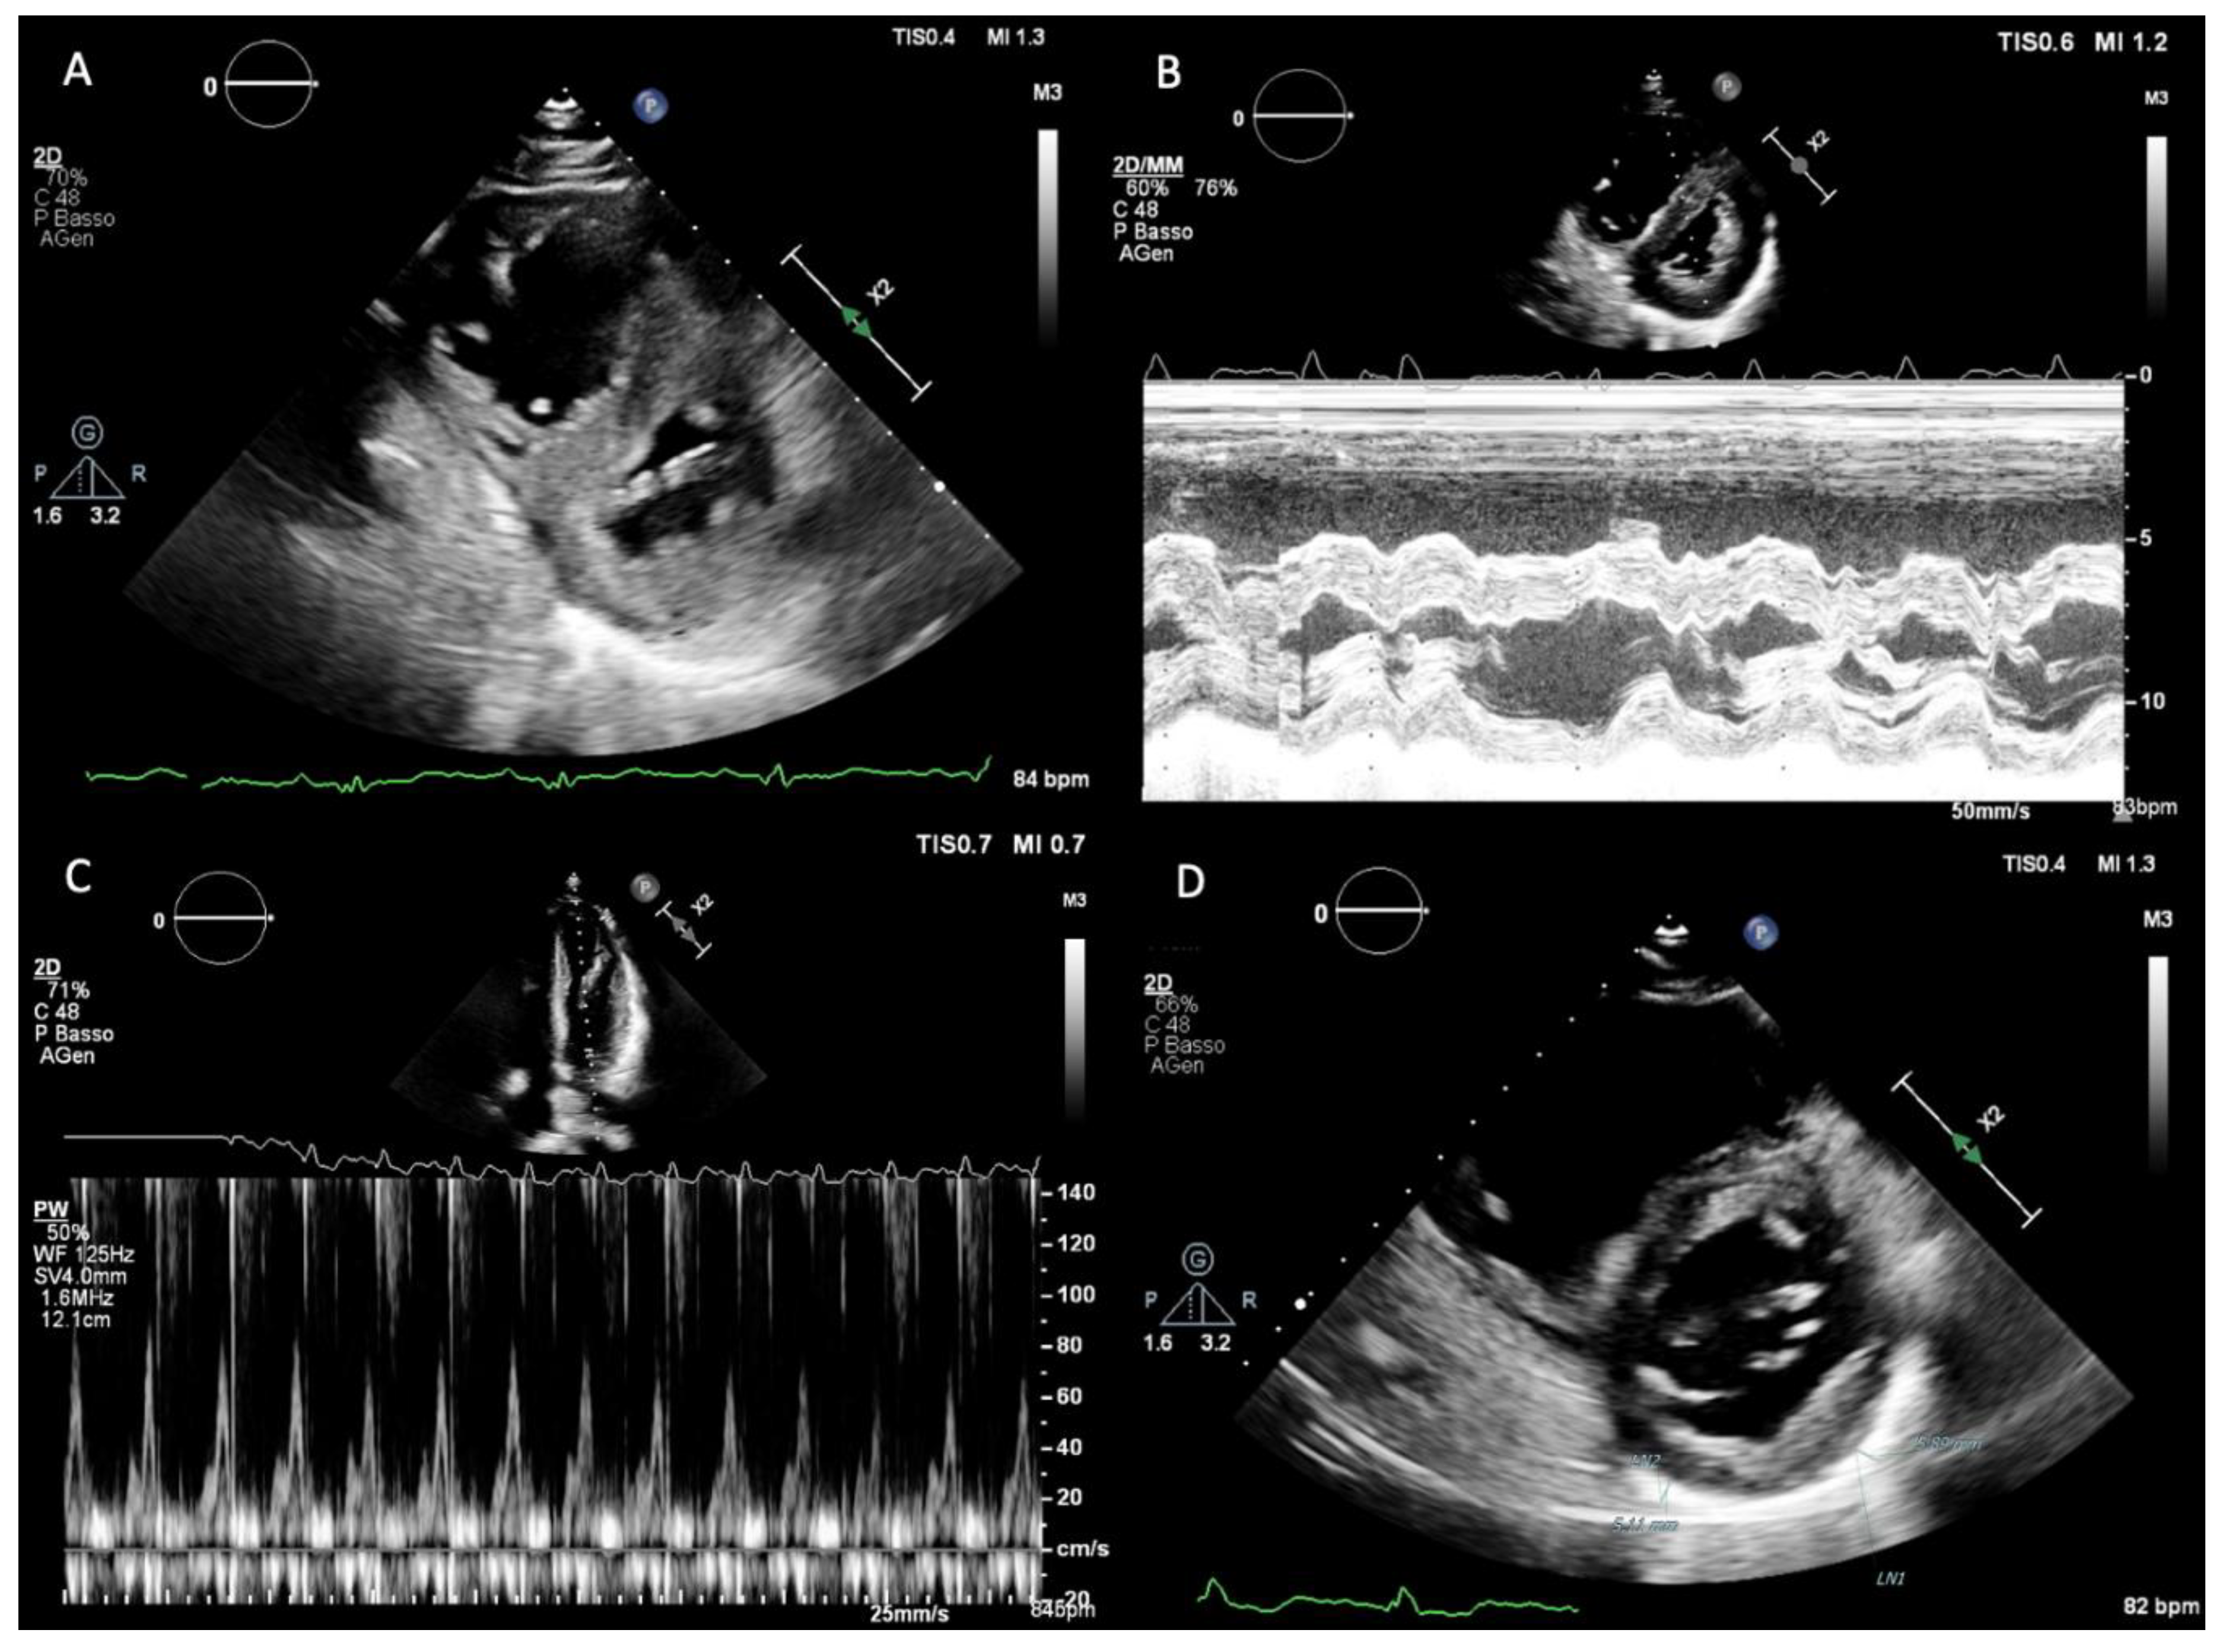

From an anatomical perspective, CT represents the reference standard for evaluating pericardial thickness, morphology, and distribution. ECG-gated contrast-enhanced CT enables precise delineation of the pericardial layers, which normally measure less than 2 mm, and allows detection of focal or circumferential thickening, asymmetric involvement, and pericardial adhesions (Figure 3.A). While a thickness >4 mm is classically considered suggestive of constriction, CT—similar to CMR—has demonstrated that a substantial proportion of patients with surgically confirmed CP may exhibit normal or only mildly increased pericardial thickness, underscoring the limited specificity of thickness alone as a diagnostic criterion [24,25]. Consequently, CT findings must be interpreted in conjunction with functional and hemodynamic data.

One of the most distinctive contributions of CT to the diagnosis of CP is the detection and characterization of pericardial calcifications (Figure 3.B). CT is markedly superior to echocardiography and CMR for identifying and mapping calcific deposits, which may be focal or diffuse and often involve the diaphragmatic surface, atrioventricular grooves, and basal ventricular segments. The presence of extensive calcification strongly supports a chronic, non-inflammatory phenotype of CP and has important therapeutic implications, as these patients are unlikely to respond to anti-inflammatory therapy and are typically referred for pericardiectomy [23,26]. Furthermore, CT allows accurate assessment of the extent, thickness, and distribution of calcifications, information that is crucial for surgical risk stratification and operative planning [24].

Figure 3. Cardiac CT findings in CP: ECG-gated contrast-enhanced CT shows focal pericardial thickening (A); ECG-gated no contrast-enhanced CT can detect the presence and extension of pericardial calcifications (B) (red arrow).